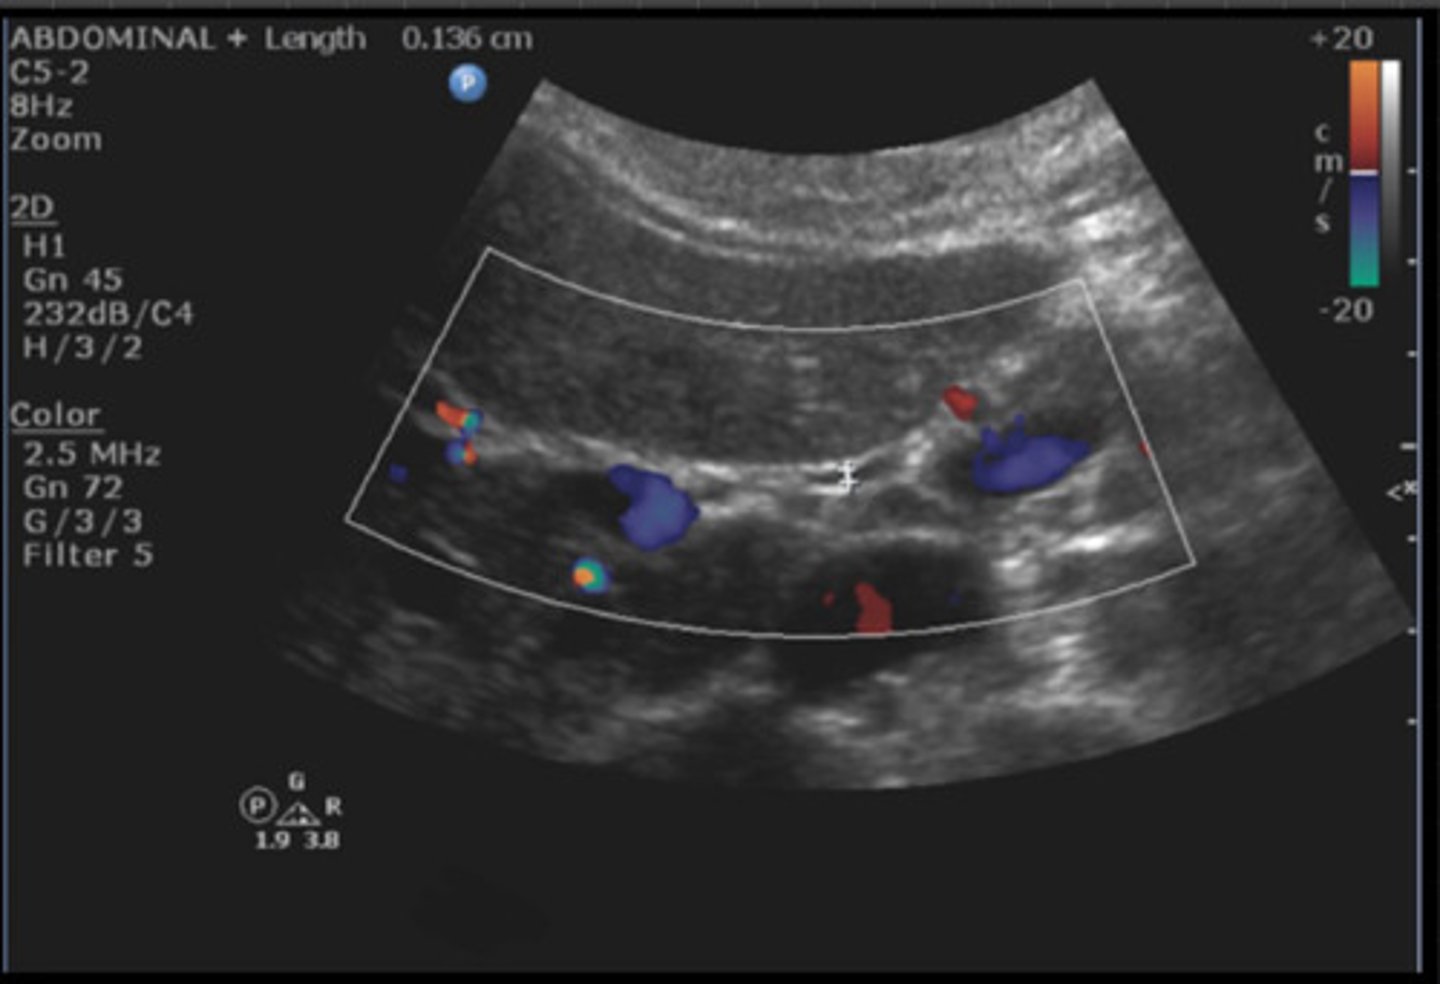

9

New cards

CBD (with measurement)

Identify the following;

<p>Identify the following;</p>